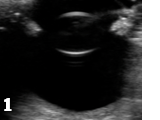

Figure 1 shows the ultrasound image of a healthy canine lens in a healthy canine eye.